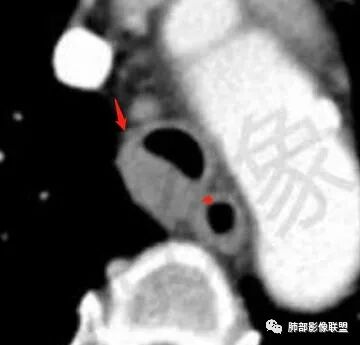

主支气管后缘外可见一实性结节,病变跨支气管管壁生长,部分突向管腔内,病变边缘光滑,平扫密度均匀,增强后尚均匀强化,纵隔淋巴结肿大不明显。

1.定位:软骨中断,非外压,而是气管本身起源,考虑恶性。与之鉴别是周围间叶起源的神经源性或平滑肌起源良性肿瘤

气管右后壁占位,平扫密度稍低于肌肉

增强后与肌肉类似,部分强于肌肉,提示强化

内外边缘光滑

宽基底与气管相连

附近壁增厚

前方见一小淋巴结,后内侧与食道联系很紧

宽基底,腔内外,看似边界清楚、光滑, 但是附近气管壁增厚,还是首先要考虑恶性,附近淋巴结也不太放心,因为强化明显

3、腺样囊性癌:是一种低级别恶性肿瘤,在气道恶性肿瘤中发病率居第2位。腺样囊性癌起源于气管黏液腺,好发于气管后壁软骨和膜部连接处,这与该部位黏液腺较多有关,肿瘤可呈息肉样或结节样突入气管,宽基底,管壁局部浸润性增厚,也可由气管黏膜下方沿管壁长轴浸润生长,至管壁不同程度增厚及相应管腔狭窄,肿瘤强化不明显。